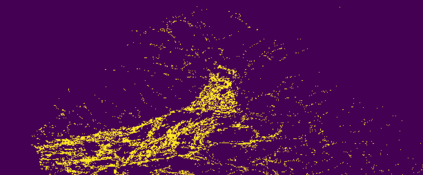

The usage of chemical imaging technologies is becoming a routine accompaniment to traditional methods in pathology. Significant technological advances have developed these next generation techniques to provide rich, spatially resolved, multidimensional chemical images. The rise of digital pathology has significantly enhanced the synergy of these imaging modalities with optical microscopy and immunohistochemistry, enhancing our understanding of the biological mechanisms and progression of diseases. Techniques such as imaging mass cytometry provide labelled multidimensional (multiplex) images of specific components used in conjunction with digital pathology techniques. These powerful techniques generate a wealth of high dimensional data that create significant challenges in data analysis. Unsupervised methods such as clustering are an attractive way to analyse these data, however, they require the selection of parameters such as the number of clusters. Here we propose a methodology to estimate the number of clusters in an automatic data-driven manner using a deep sparse autoencoder to embed the data into a lower dimensional space. We compute the density of regions in the embedded space, the majority of which are empty, enabling the high density regions to be detected as outliers and provide an estimate for the number of clusters. This framework provides a fully unsupervised and data-driven method to analyse multidimensional data. In this work we demonstrate our method using 45 multiplex imaging mass cytometry datasets. Moreover, our model is trained using only one of the datasets and the learned embedding is applied to the remaining 44 images providing an efficient process for data analysis. Finally, we demonstrate the high computational efficiency of our method which is two orders of magnitude faster than estimating via computing the sum squared distances as a function of cluster number.